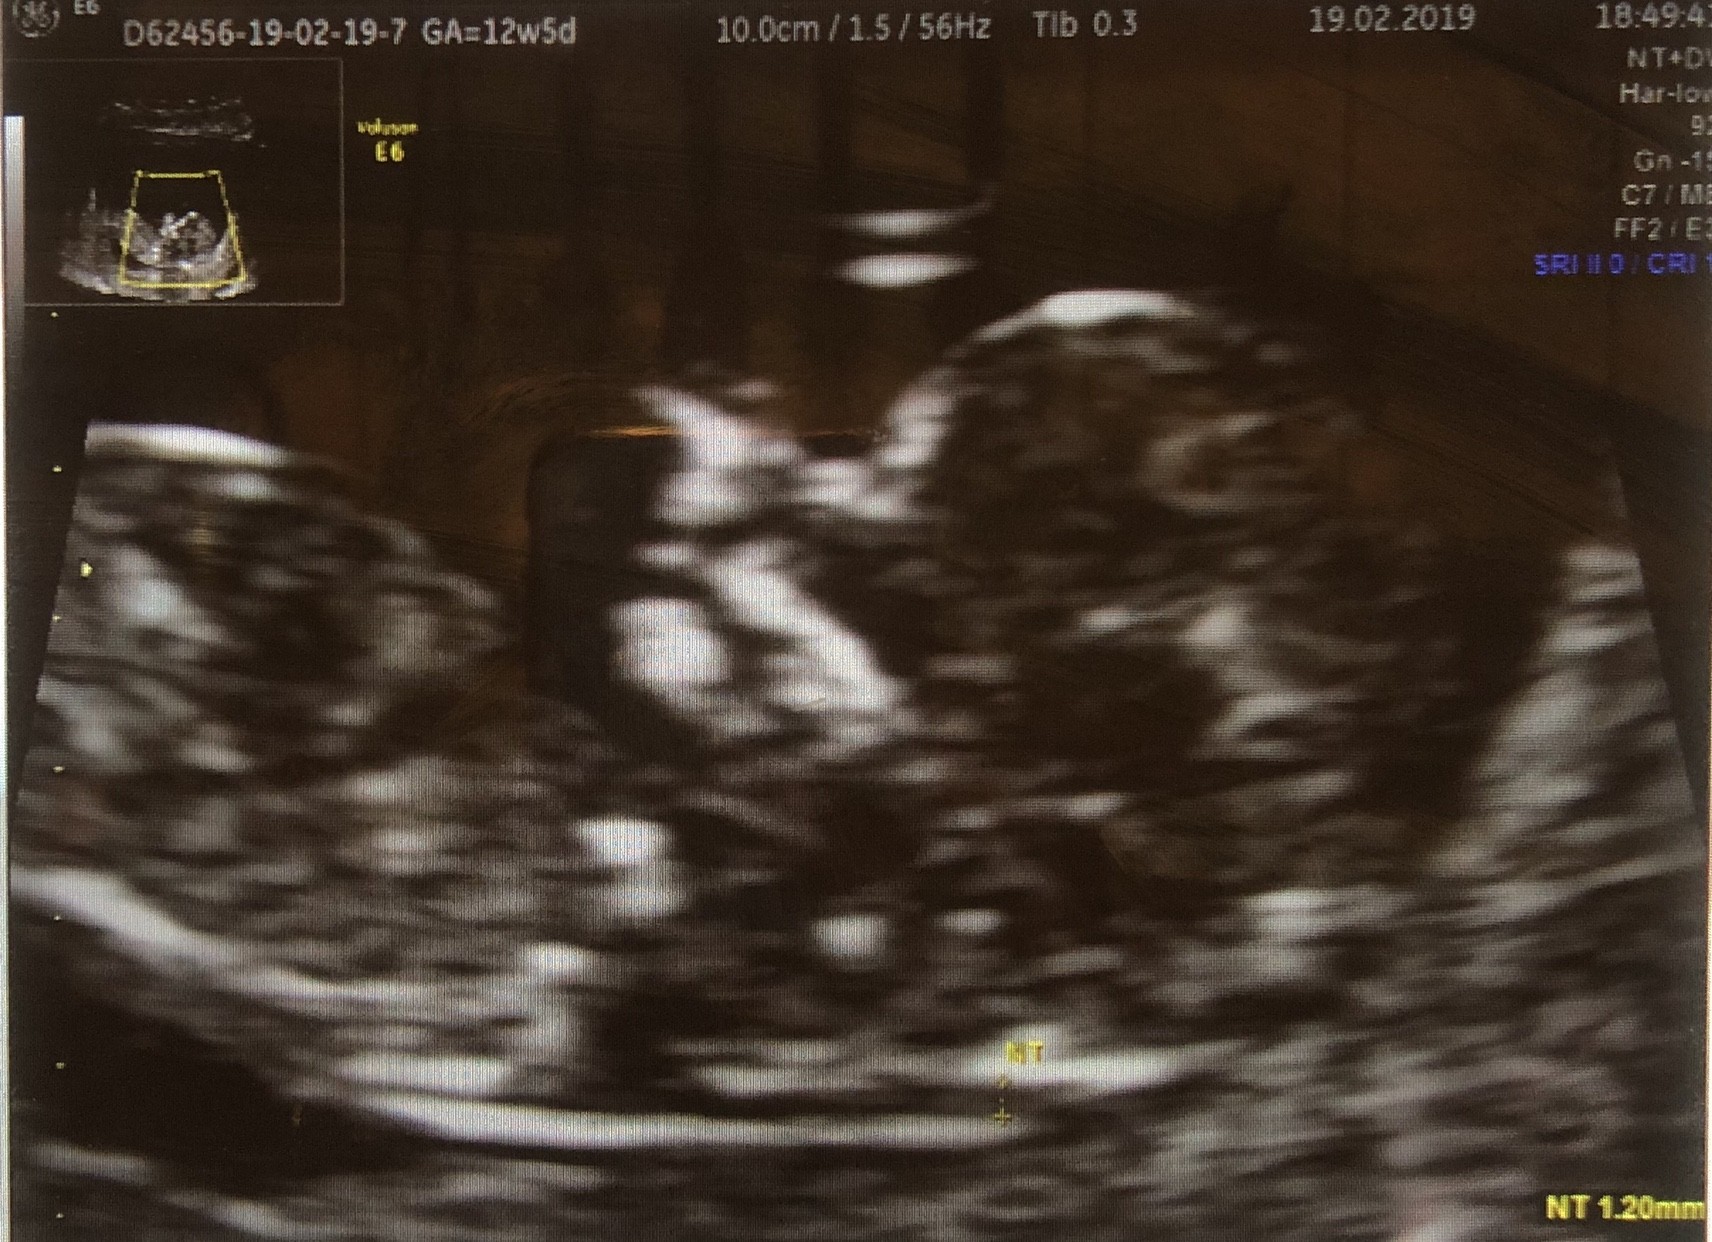

Ja po usg. Naczekalam się z godzinę a USG trwało nawet nie 5minut. Widziałam pięknego maluszka wiercipięte, crl to 45mm. Niby wszystko ok ale zmierzył nt i wyniosło 2,3. W normie jeszcze ale już się martwię. Tym bardziej że kości nosowej nie szukał poinformował mnie że są badania prenatalne za darmo i jak usłyszał że już się zapisałam to skończył USG :/Tp mi się przesunął na 7.09.

kilka godzin siedziałam i patrzyłam się w zdjęcie które jest tak nie wyraźne jak sroka w gnat i próbuje się tam dopatrzyć noska. Dobrze że teraz wyszłam z młodym na trening. Za tydzien mam prenatalne. Mam nadzieję że będą dłuższe i więcej się dowiem.